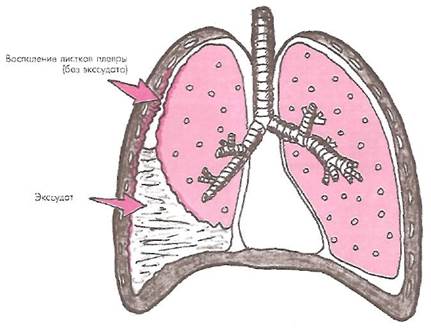

Рис. 3 . Механизм образования плеврального выпота при воспалении плевры. Схематически показано значительное увеличение секреции (экссудация) и уменьшение реабсорбции плевральной жидкости.

Традиционное деление плевритов на фибринозный (сухой) и выпотной (экссудативный) достаточно условно, поскольку в подавляющем большинстве случаев сухой плеврит является лишь первой начальной стадией формирования выпотного (экссудативного) плеврита. При небольшой экссудации и достаточной скорости резорбции воспалительной плевральной жидкости небольшое количество фибринозного экссудата удерживается локально в области воспаления плевральных листков (рис. 6.10). Если по каким-либо причинам воспалительный процесс в плевре стабилизируется и в дальнейшем не прогрессирует, на листках плевры откладывается фибринная пленка, постепенно уменьшается воспалительная экссудация и заболевание претерпевает обратное развитие. Такие случаи расцениваются как проявления фибринозного (сухого) плеврита.

Рис. 10. Сухой плеврит (схема)

Если же стабилизации воспалительного процесса в плевре не происходит, нарастает экссудация, заметно снижается резорбция плевральной жидкости, то объем плеврального выпота увеличивается и формируется выпотной (экссудативный) плеврит (см. рис. 3).